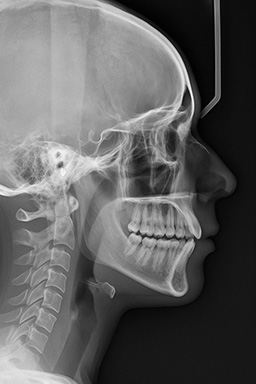

Telerradiografía Lateral de Cráneo

Imagen cefalométrica de alta precisión para diagnóstico ortodóncico y planificación de tratamientos dentofaciales.

La telerradiografía lateral de cráneo permite observar el perfil óseo y de tejidos blandos del paciente. Es fundamental en ortodoncia para realizar análisis cefalométricos, estudios de crecimiento y planificación de tratamientos quirúrgicos maxilofaciales.